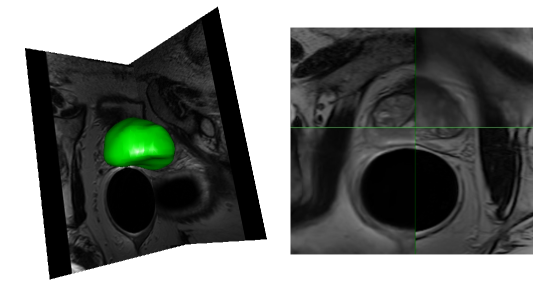

Refer to caption

Figure 5: Automatic segmentation – deformated atlas ; from the left to the right : 3D view of automatic segmentations, fusion of deformed atlas (top right / bottom left) and study image (top left / bottom right)